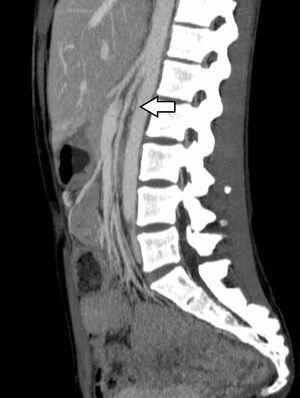

Se practicó una angio-tomografía computarizada, que ya no demostró la presencia de trombosis de la vena cava inferior, pero sí trombosis de la vena renal y la vena ovárica izquierda (figura 1), así como una estenosis de la vena renal izquierda en su paso entre la aorta y la arteria mesentérica superior, compatible con un SCN (figura 2).

Figura 1. Trombosis de la vena renal izquierda y compresión de esta durante su paso entre la aorta y la mesentérica superior compatible con síndrome del cascanueces.